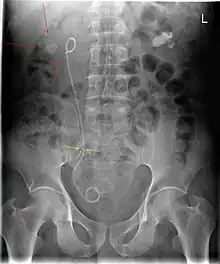

A ureteral stent (pronounced you-REE-ter-ul), or ureteric stent, is a thin tube inserted into the ureter to prevent or treat obstruction of the urine flow from the kidney. The length of the stents used in adult patients varies between 24 and 30 cm. Additionally, stents come in differing diameters or gauges, to fit different size ureters. The stent is usually inserted with the aid of a cystoscope. One or both ends of the stent may be coiled to prevent it from moving out of place; this is called a JJ stent, double J stent or pig-tail stent.

Ureteral pigtail stent | |